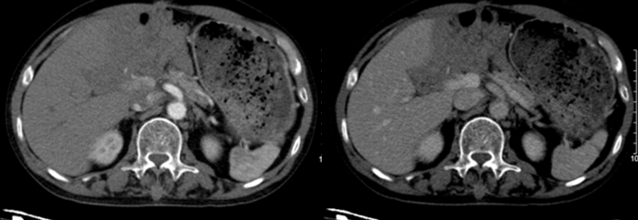

- Chụp cắt lớp vi tính lồng ngực: Hình ảnh tổn thương xơ đỉnh phổi phải. Không phát hiện các khối, nốt bất thường.

Hình 3: Hình ảnh CT lồng ngực: nhu mô ở cả hai phổi không phát hiện các tổn thương bất thường.